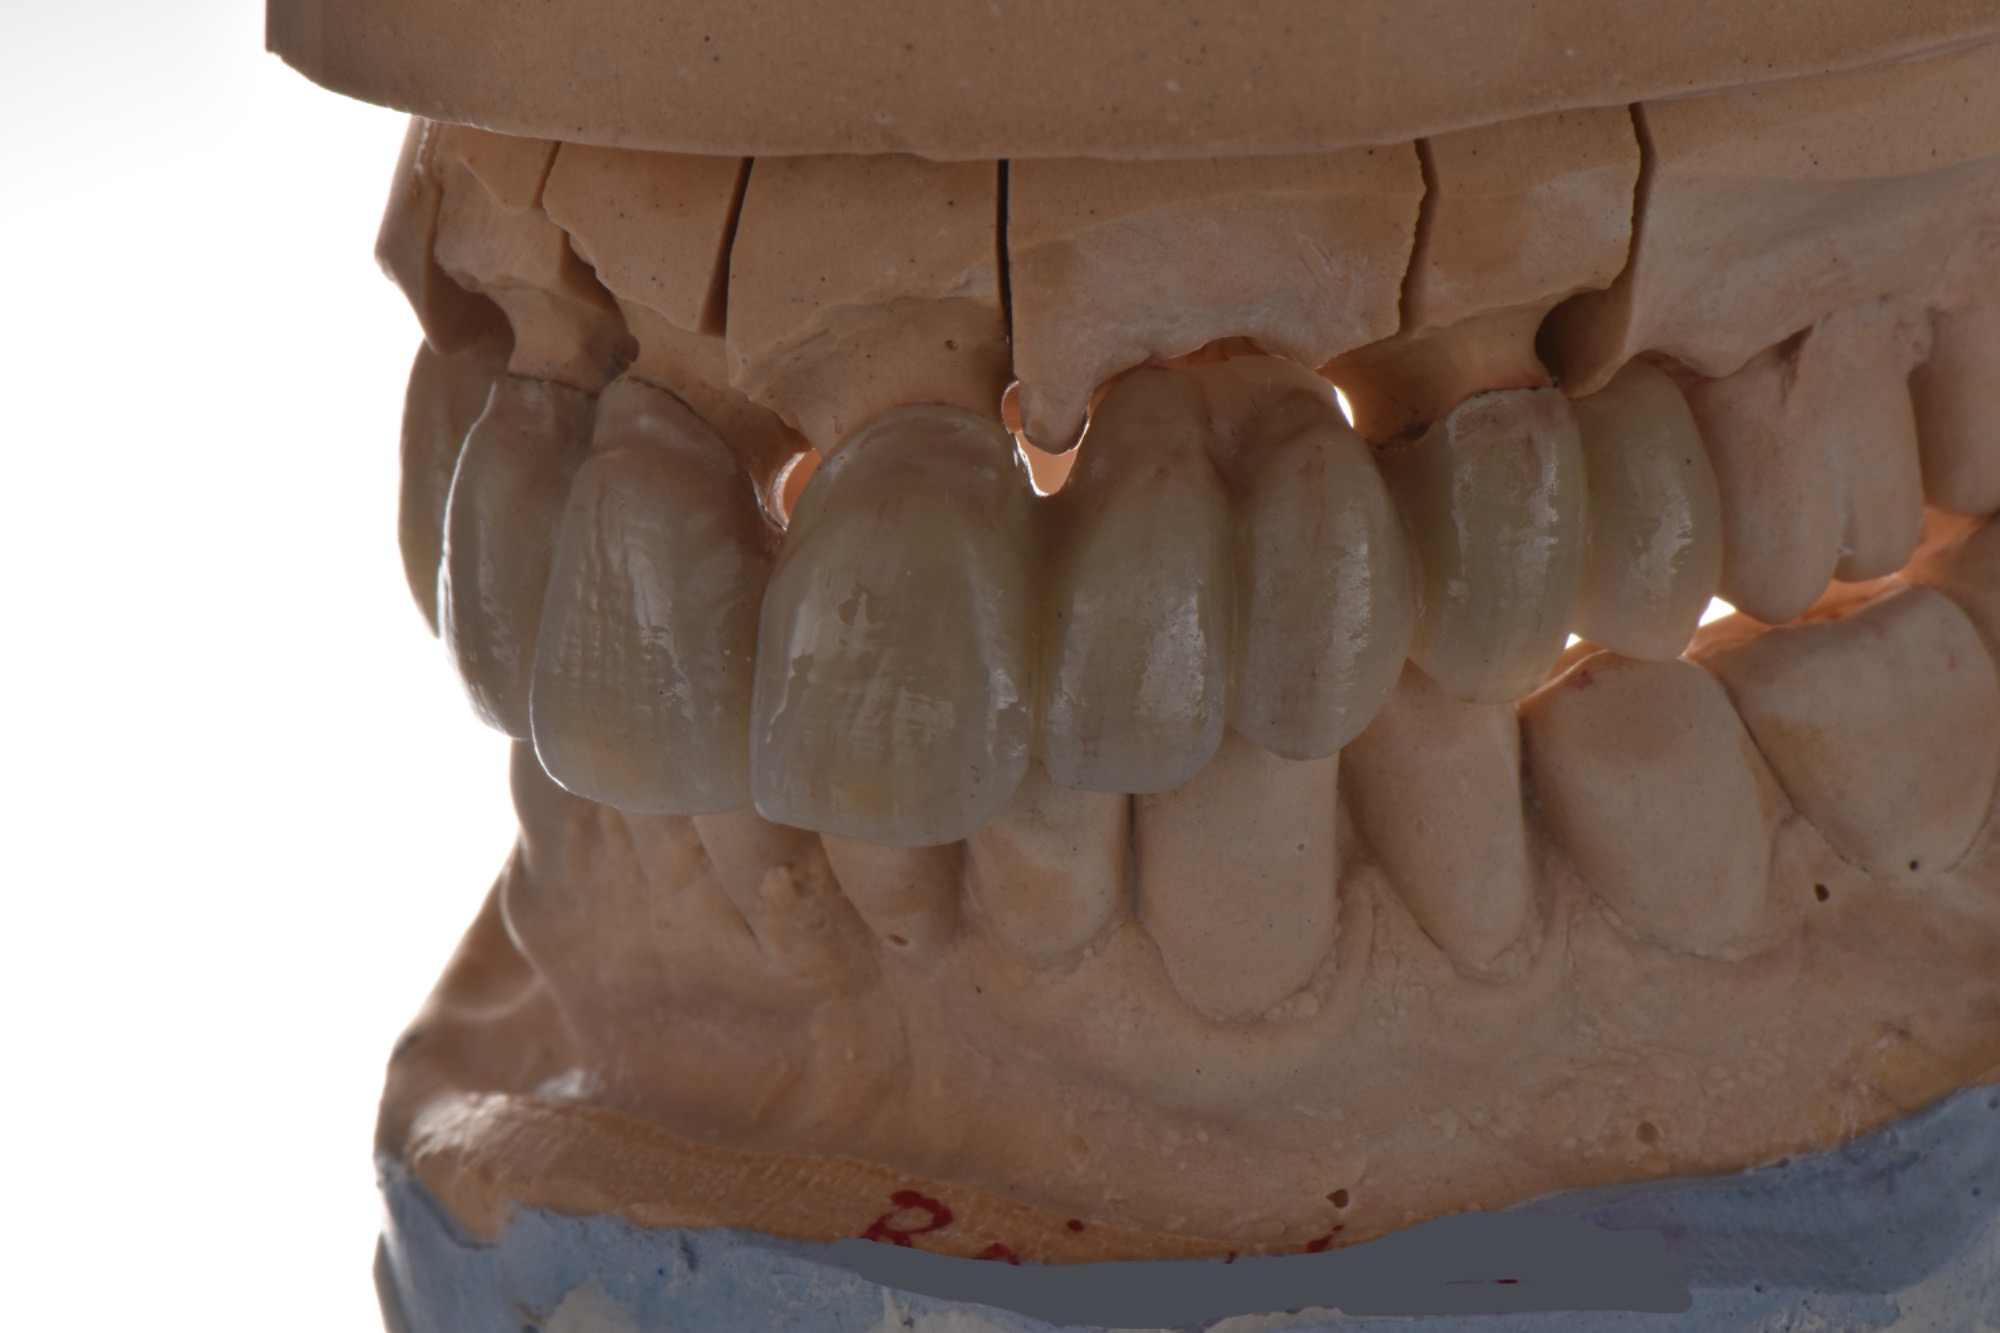

Metallfreie Frontzahnkronen mit individueller keramischer Verblendung.